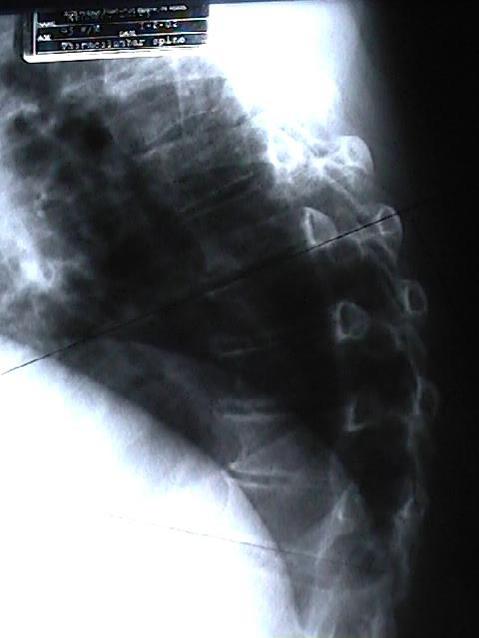

Well, the spine’s uprightness allows us humans to wander around our Fort Wayne worlds with ease: eyes forward, head up, feet one step in front of the other. The gentle curves balance us well. Normal. This normal state is how most Fort Wayne folks exist thankfully. On the other hand, a few Fort Wayne people find themselves with back pain conditions that are not normal and actually cause pain. One such condition is ankylosing spondylitis (AS), a condition Cox Chiropractic Medicine Inc finds to be quite responsive to Fort Wayne chiropractic care. But first, more about AS and the latest findings.

Now, medical literature points out that AS patients have a 5-fold higher risk of clinical spine fracture and a 35% increased risk of non-vertebral fracture. This extra risk peaks early, in the first 2 and a half years of AS disease. It is recommended that AS patients be assessed for fracture risk early after their AS diagnosis. (3) Trust Cox Chiropractic Medicine Inc to do this for you or your loved one with AS.